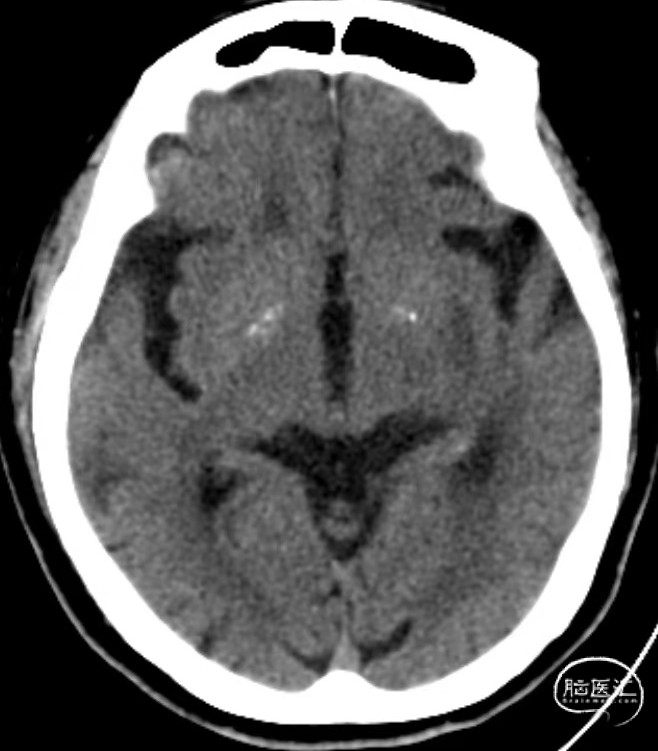

术后即刻复查CT,未见出血及造影剂渗出。